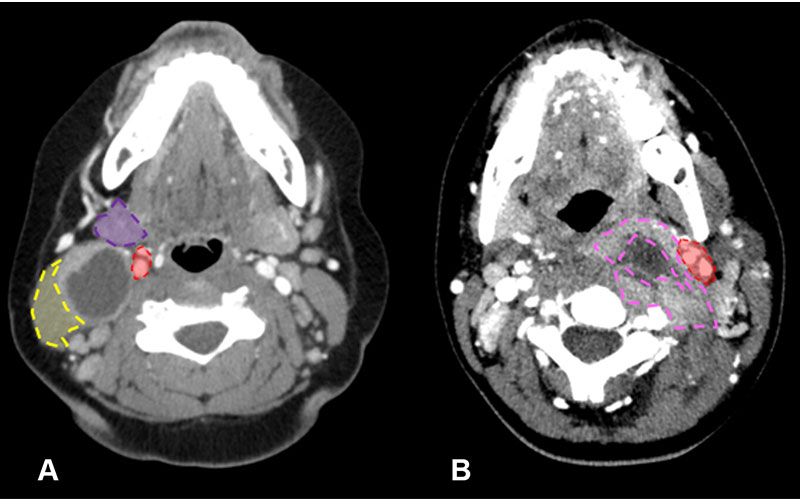

Distinction between branchial cleft cyst and retropharyngeal abscess in two pediatric patients who visited the emergency department due to neck pain and swelling. (A) Axial CT image of the neck in a 10-year-old girl shows typical imaging characteristics strongly indicative of a branchial cleft cyst. This is evident from the lesion location posterior to the submandibular gland (purple shaded area), lateral to the carotid space (red shaded area), and anteromedial to the sternocleidomastoid muscle (yellow shaded area). (B) Axial CT image in a 12-year-old girl conversely shows features that align more with a retropharyngeal abscess. This is characterized by an irregular and thick enhancing wall (pink dashed outline), accompanied by surrounding fat stranding and edema. Notably, this lesion is situated medially to the carotid space (red shaded area). (See slide 35 in the accompanying presentation.)